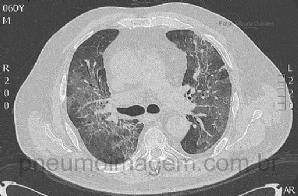

CASO CLÍNICO #10

Paciente do sexo masculino, 60 anos, com histórico de quadro gripal há 4 dias associado à febre. Há um dia com dispneia, tosse produtiva, deu entrada no Serviço de Emergência em insuficiência respiratória e importante dessaturação. Nega antecedentes pulmonares...